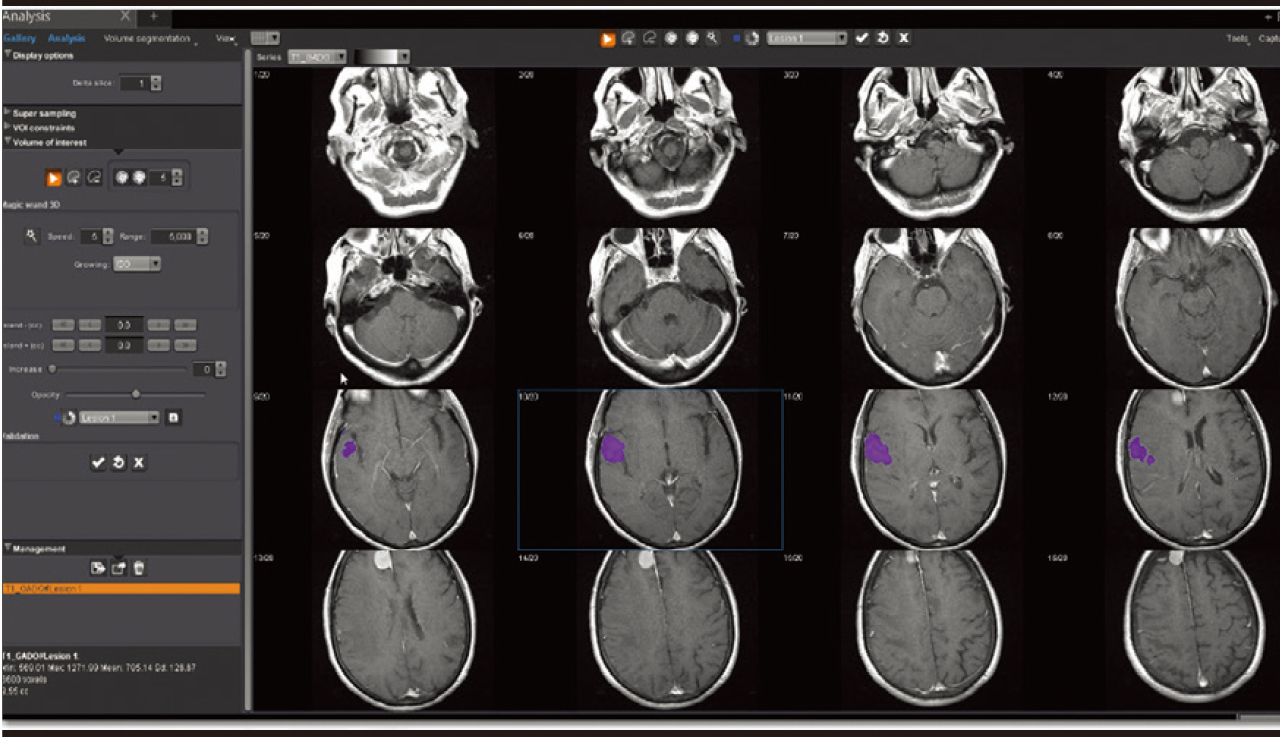

Додаток Аналіз візуалізує, сегментує, вимірює та оцінює широкий спектр наборів даних від звичайних серій до перфузійних та кінетичних серій разом із серіями DTI та DWI. Він забезпечує визначені користувачем накладання, включаючи візуалізацію органу/або патології, аналіз кінетики та кривих, аналіз кривих, статистику, співвідношення та гістограми, синтез декількох серій, напівавтоматичне сегментування об’єму, рендеринг об’єму та подальші динамічні спостереження.

Додаток Brain Tumor Streamlined.

Додаток Brain Tumor пропонує автоматизовану покрокову обробку, включаючи кількісний мультипараметричний аналіз. Ця програма також включає оптимізований алгоритм корекції витоку контрастної речовини для підвищення точності оцінки DSC MР-перфузії.